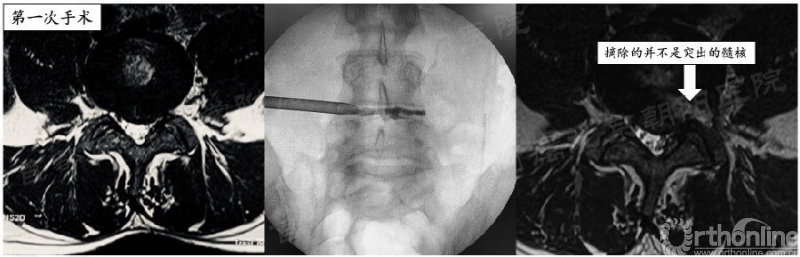

我就不做或做不好成型会怎样呢?举一例反面病例,也是前30例中唯一因手术效果不佳行二次手术的患者:

患者33岁美籍白人男性,L4/5节段II区突出,第一次手术由于通道角度不理想,同时未行充分关节突成型,未能将突出的髓核摘出,手术效果不理想。在二次手术时调整通道方向,同时行3级关节突成型,实现了对神经的彻底减压(见视频6-1,6-2)。

见视频6-1,6-2(待完善)